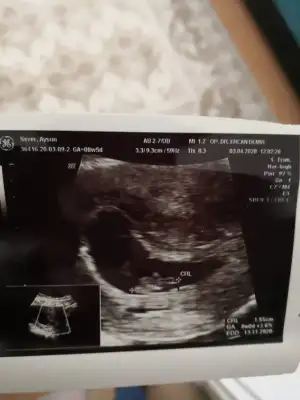

8 hafta ya göre erkek ama siz 11 12 13 hafta nub için paylaşınbize de tahmin yaparmısınız. ikisi de karından usg. ilk resim 9+4 ikincisi 8

Buna göre kızKarindan usg 7+4kizlar yorum yapacak olan varsa cok mutlu olurum

Bundan sonra gidemeyecgm sanirim cinsiyet vakti 14 15 .haftalar giderim nasil anladiniz kiz acabaBuna göre kızama siz 11 12 13 hafta nub için paylaşın

Çok tesekkur ederim zahmet olmasa buna da bakabilir misiniz kardesimin 8 haftalikBuna göre kızama siz 11 12 13 hafta nub için paylaşın

Buda kız yolksac göre bakıyorumÇok tesekkur ederim zahmet olmasa buna da bakabilir misiniz kardesimin 8 haftalik